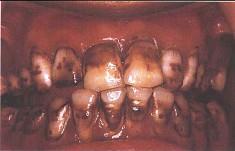

问题 关于氟斑牙,下列哪个说法是错误()

选项 A.氟主要损害釉质发育期牙胚的造釉细胞 B.饮用水是摄人氟的最大来源 C.深层釉质含氟量是表面釉质的11倍左右 D.又称斑釉牙 E.慢性氟中毒患者可有骨骼增殖性变化

答案 C